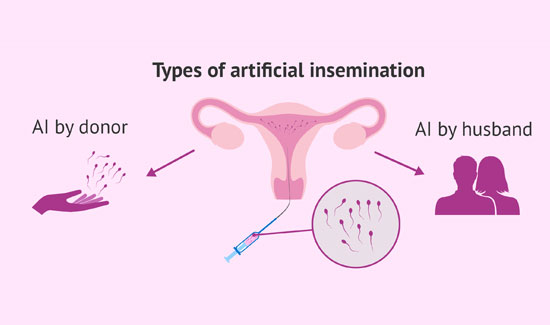

Artificial Insemination Homologous

Artificial Insemination Donor Super Ovulation and Intra Uterine Insemination